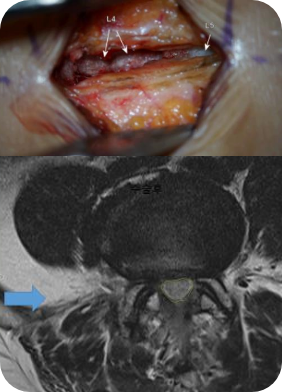

척추에 오는 대표적인 3대 질환 중 전방전위증 혹은 협착증이 여러 곳 있거나 척추의 옆 구멍이 막힌 경우 대개 많은 의사들은 환자들에게 나사못 고정술을 권합니다. 현미경 혹은 내시경을 이용하더라도 이런 나사못 고정술은 환자에게 결국 장애를 남기는 수술법입니다. 좋은아침병원은 내시경의 장점과 현미경의 장점을 결합한 MILD 수술을 개발하여 나사못 고정술을 피할 수 있는 솔루션을 제공하고 있습니다.